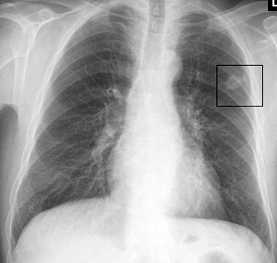

Прямым показанием к проведению КТ служит обнаружение при флюорогрофическом исследовании или при рентгенографии четко очаговой тени на снимке. Конечно, рак легких на рентгене выглядит не очень специфично - ведь похожие изменения могут быть обусловлены также туберкулезом, другими доброкачественными опухолями, и даже пневмонией. Все эти состояния могут быть дифференцированы с помощью КТ.

Рентгенография при раке легкого выявляет округлую тень слева. С целью дифференциальной диагностики (отличить рак легкого от туберкуломы, кисты или пневмонии) необходимо выполнять компьютерную томографию — КТ.